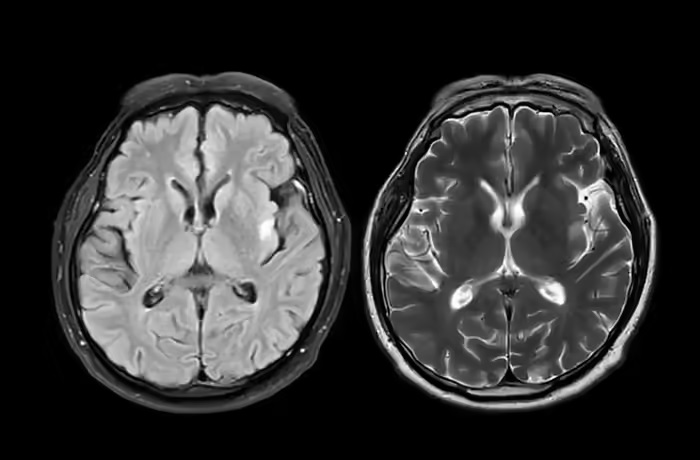

MRI में हुआ चौंकाने वाला खुलासा

आंद्रे के 23वें जन्मदिन से ठीक पहले MRI किया गया। इसमें स्पष्ट हुआ कि आंद्रे को फ्रंटोटेम्पोरल डिमेंशिया है। डॉक्टरों ने बताया कि उसका दिमाग अब 70 साल के बुज़ुर्ग व्यक्ति जैसा काम कर रहा था। यह परिवार के लिए बहुत ही दुखद और चौंकाने वाला खुलासा था।